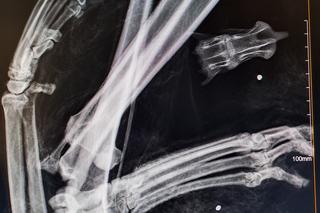

"Cleo, została znaleziona w okolicach Piasecznika (gm. Choszczno) w stanie rozkładu" - informują przyrodnicy. - "Po zbadaniu ciała w jej szczątkach zabezpieczono kilka śrucin".